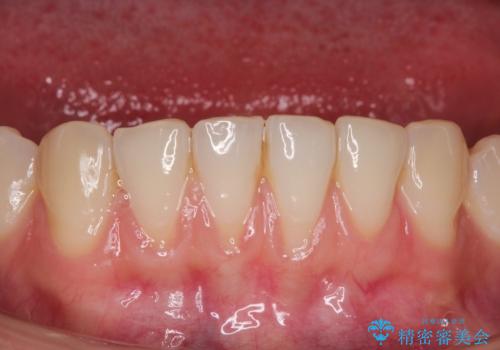

長く見えてしまう下顎前歯 歯肉移植術で露出した歯根を覆い隠す

担当医 藤巻太一朗